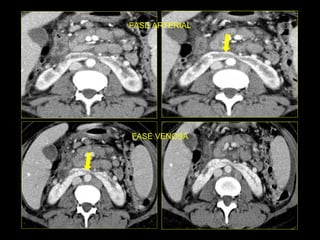

Caso # 7 ♀ , 45 años,  dolor abdominal difuso, sin poder determinarse la causa clínicamente por lo que se envía a TC para búsqueda de la probable causa de dolor. Estudio en fases arterial, venosa y excretora, mostrándose cortes axiales.

FASE ARTERIAL

FASE VENOSA

Hallazgos Caso # 7: Hay un área triangular de disminución de la atenuación en la parte posterolateral del  riñón izquierdo, las cuales se demuestran en fases contrastadas, y en fase excretora muestran persistencia del medio de contraste, en relación con proceso inflamatorio focal.